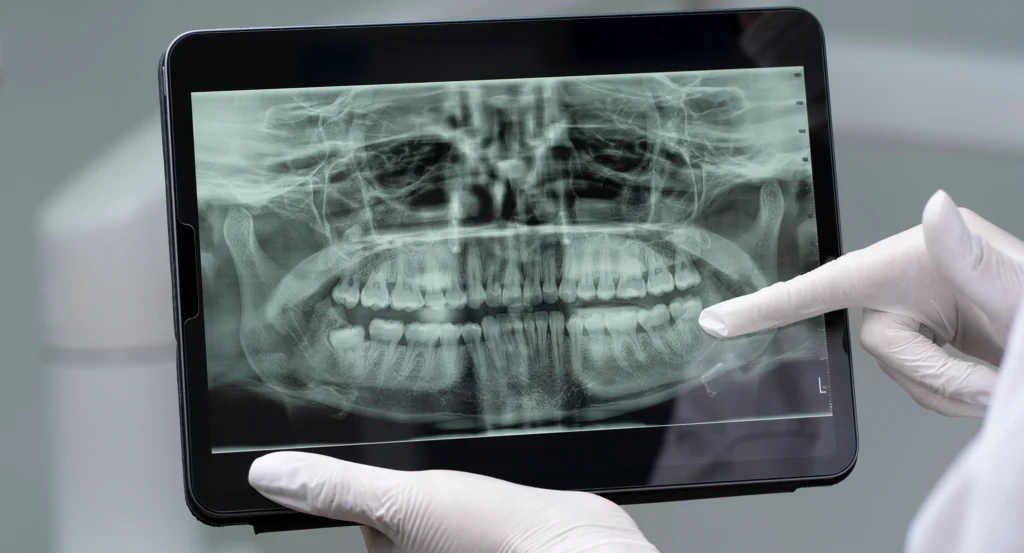

Our clinic in Tricity is fully equipped with 3D CBCT / OPG, digital planning tools and modern surgical setups. Everything – from your first scan to your final crown or bridge – happens under one roof with a team that knows your case inside out.

In many places, implants are still placed using only 2D X‑rays and the dentist’s feel for the bone. It can work, but there’s always some uncertainty about exactly how much bone is available, where the nerve runs or how close the sinus is.

With CBCT‑guided implants, we remove that uncertainty.

At Gelos Dentistry, we start with an in‑house 3D CBCT scan. This gives us a clear, three‑dimensional view of your jaws – bone height, width, density, nerve canals, sinus spaces – everything we need to see before touching the bone. On a computer, we then plan where each implant should go, at what angle, and to what depth.

If implants look like a good option, we move to a 3D CBCT scan. The scan is quick and painless; you simply stand still while the machine rotates around your head. Within minutes, we can see detailed cross‑sections of your jaws on the screen.

This step is done right at our dental clinic in Tricity, so there’s no waiting for reports to come from a different centre.